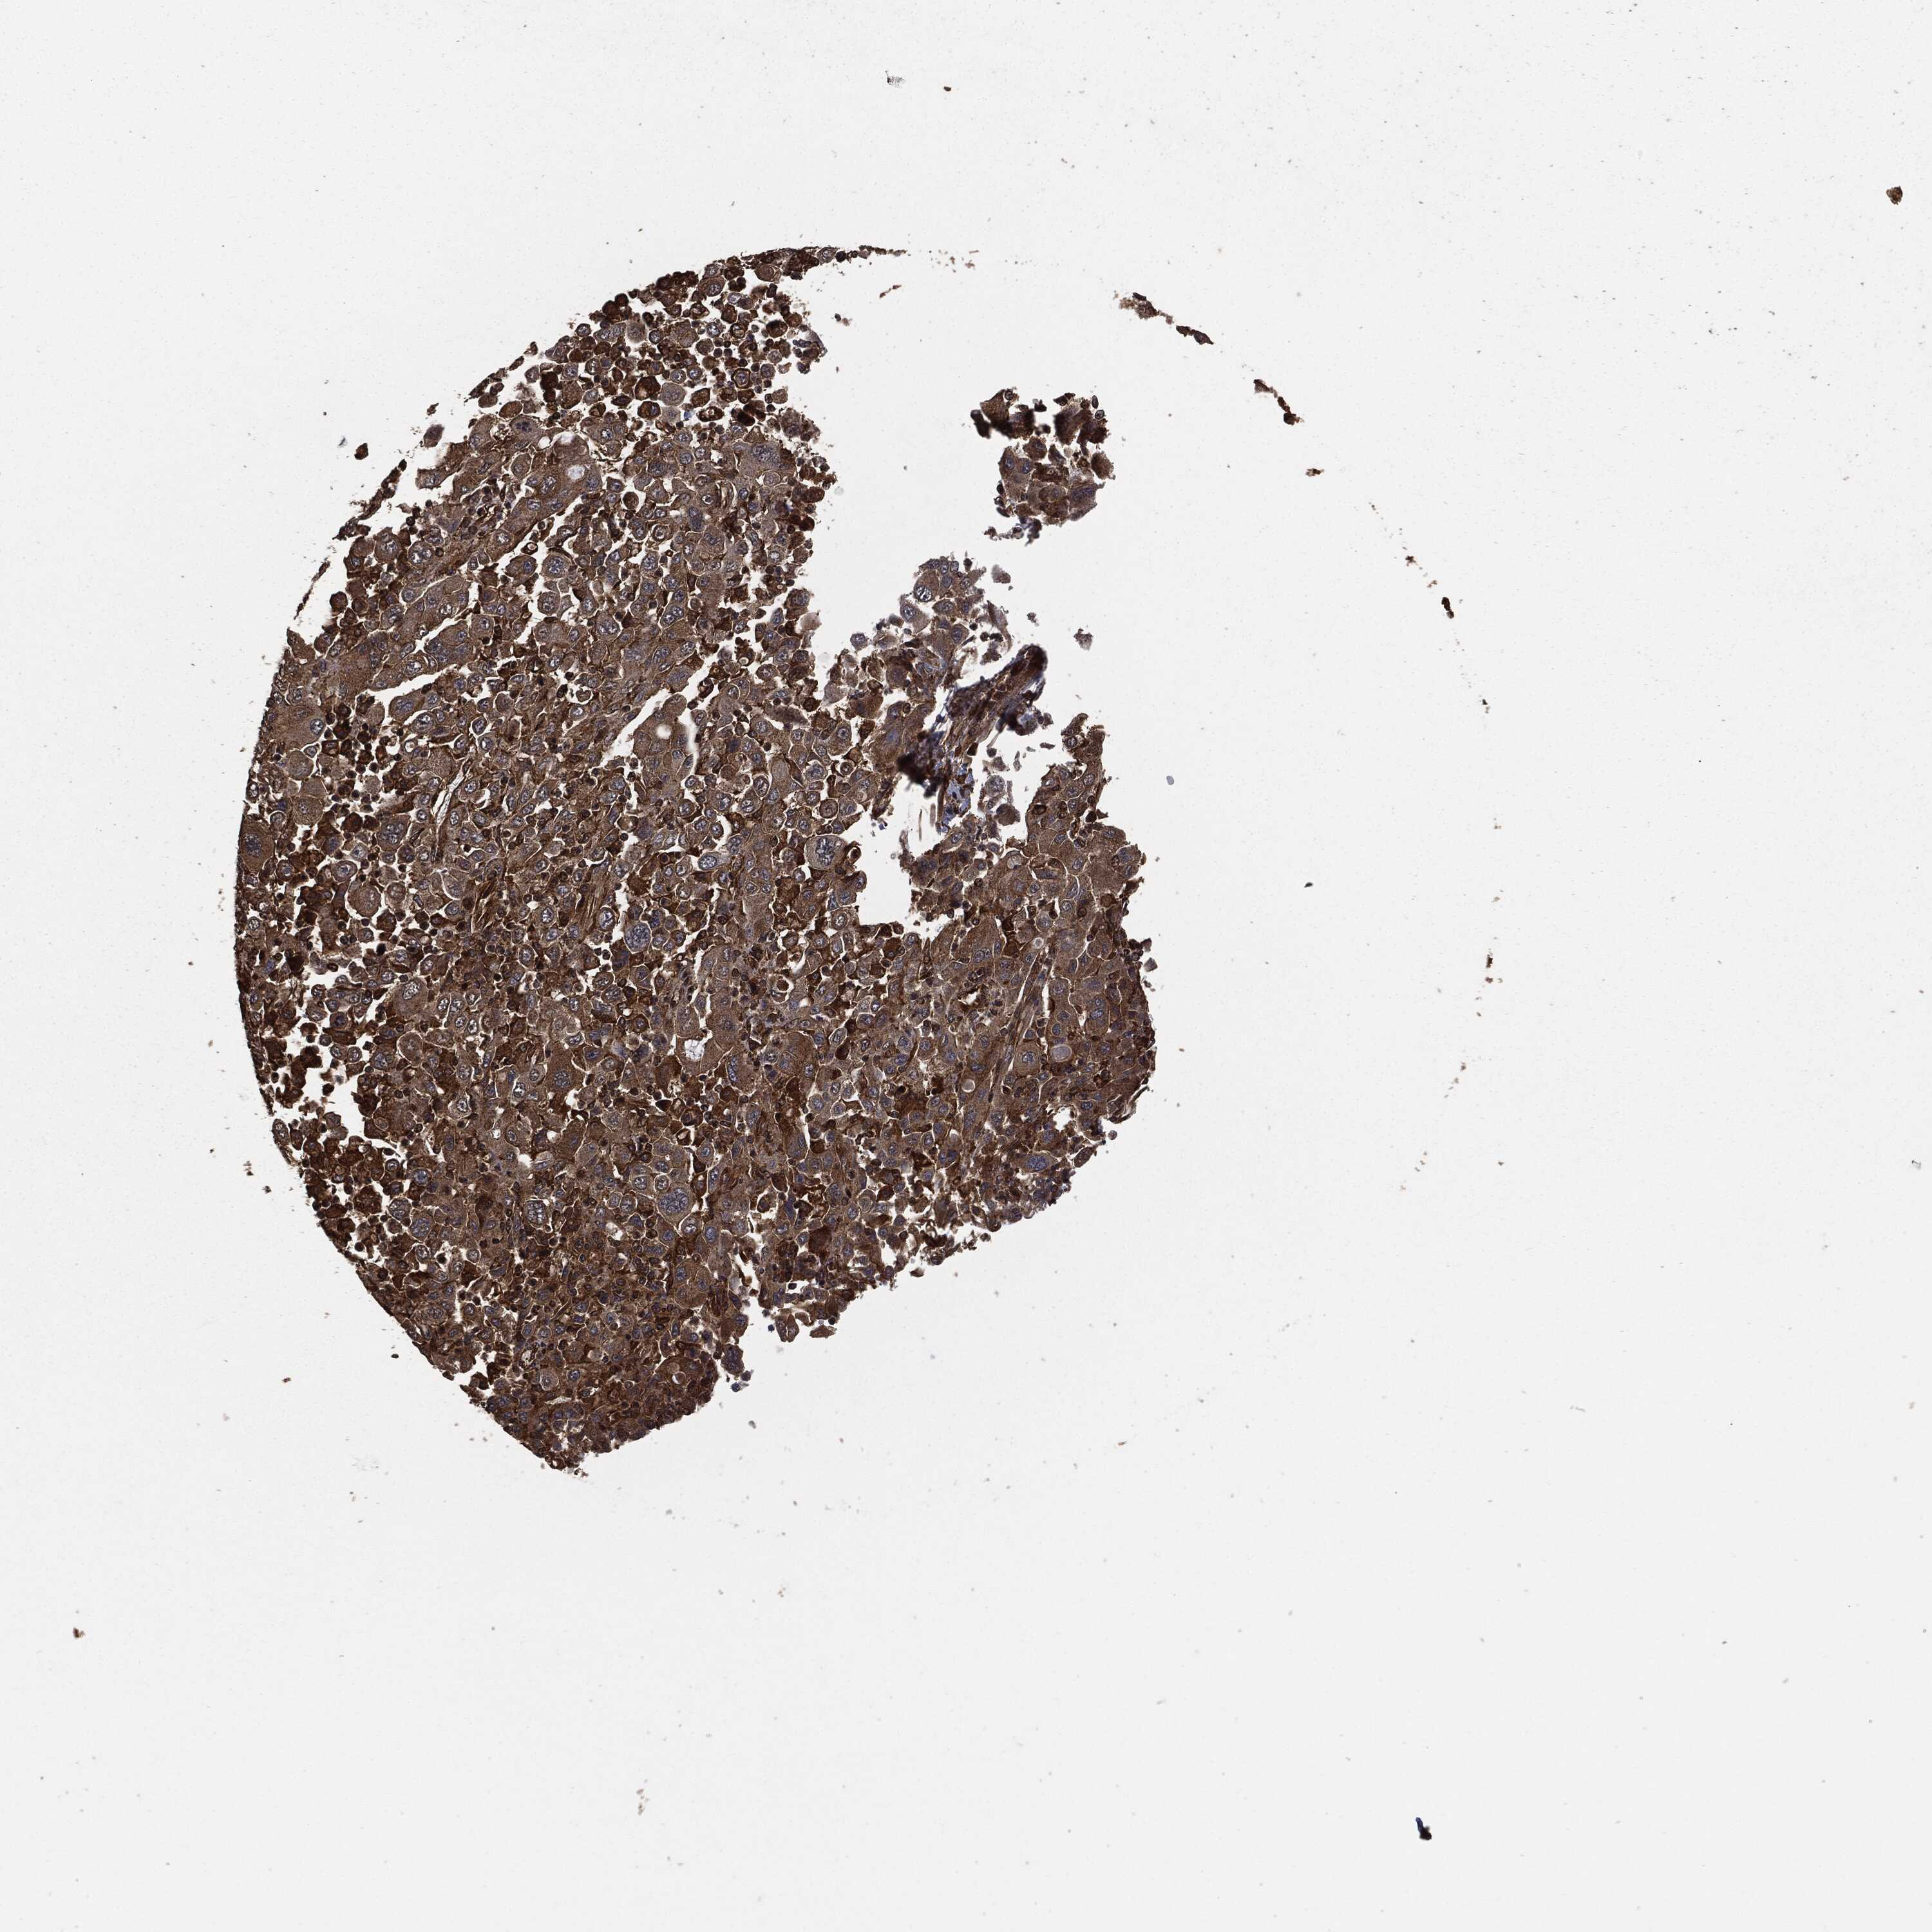

STOMACH CANCER - Protein expressioni

A mouse-over function shows sample information and annotation data. Click on an image to view it in a full screen mode. Samples can be filtered based on level of antibody staining by selecting one or several of the following categories: high, medium, low and not detected. The assay and annotation is described here.

Note that samples used for immunohistochemistry by the Human Protein Atlas do not correspond to samples in the TCGA dataset.

Antibody stainingi

Antibody staining in the annotated cell types in the current human tissue is reported as not detected, low, medium, or high, based on conventional immunohistochemistry profiling in selected tissues. This score is based on the combination of the staining intensity and fraction of stained cells.

Each image is clickable and will lead to virtual microscopy that enables deeper exploration of all samples and also displays staining intensity scores, fraction scores and subcellular localization as well as patient and tissue information for each sample.

HPA049830

CAB002015

CAB080330

CAB080331

CAB080332

Staining

High

Medium

Low

Not detected

Intensity

Strong

Moderate

Weak

Negative

Quantity

>75%

75%-25%

<25%

None

Location

Nuclear

Cytoplasmic/membranous

Cytoplasmic/membranous,nuclear

Adenocarcinoma, NOS

Adenocarcinoma, High grade